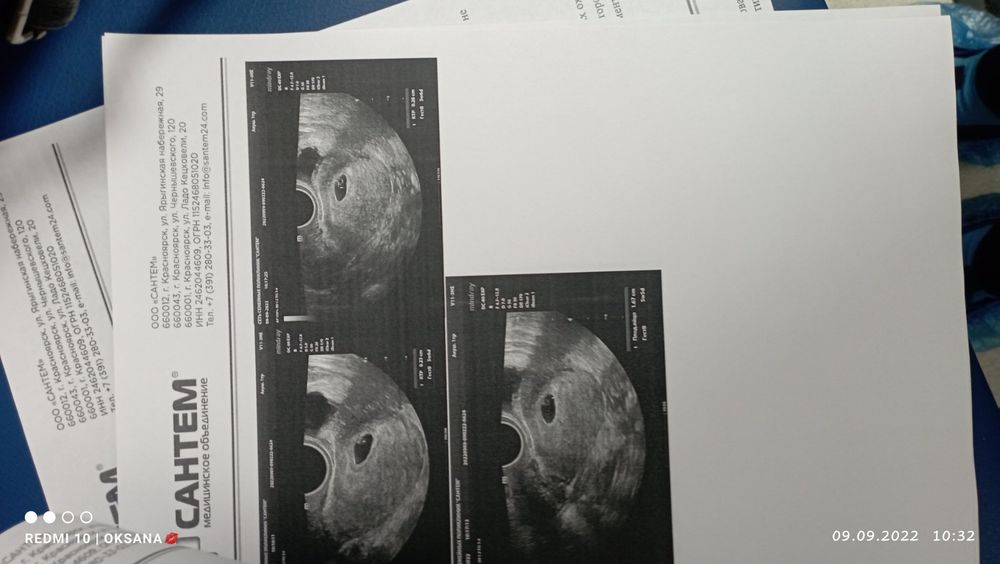

Первое УЗИ моё

Беременность- 1 триместр ( только до 10 недель)

Девочки подскажите норма или нет? Не видят желточный мешок на УЗИ